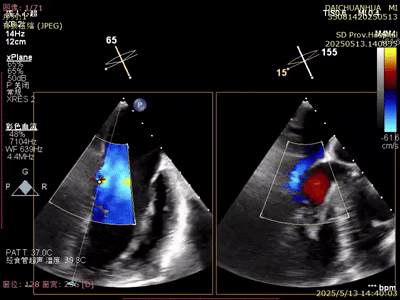

術(shù)后超聲

反流變?yōu)檩p度,反流等級(jí)從4+降為1+;

術(shù)后平均跨瓣壓差1mmHg;

夾子夾合量:前葉15mm,后葉10mm;

剩余瓣環(huán)面積:術(shù)后有效瓣環(huán)面積3.7cm²;

二尖瓣3區(qū)可見(jiàn)夾子強(qiáng)回聲,位置固定。